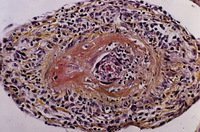

Espécime de biópsia mostrando inflamação transmural visível de uma pequena artéria

Do acervo do Dr Loic Guillevin